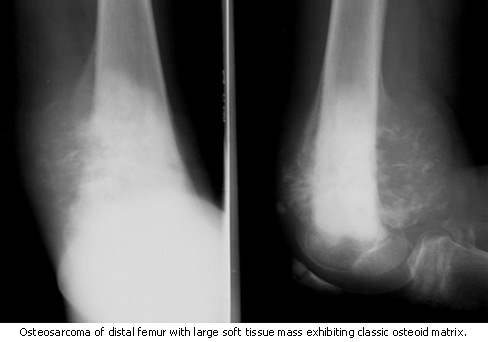

Osteosarcoma

Osteosarcoma is the most common type of primary bone cancer, making up 35 percent of bone cancer cases. This cancer affects primarily children and young adults between the ages of 10 and 25. Osteosarcoma often starts in the ends of bones, where new tissue forms as children grow. It arises most often in the knee.

A physician will usually order imaging tests such as an x-ray, which will allow the doctor to see any unusual bone growths. This may be followed by a bone scan, to see if there are other abnormal areas in the skeleton. Before a bone scan, a small amount of "tracer" material is injected into a vein. After a few hours, this tracer material, which is slightly radioactive, collects in places where there is new bone growth. A CT (computed tomography) or MRI (magnetic resonance imaging) scan is often ordered to show the exact size and shape of the suspected bone tumor, and to determine if it has invaded surrounding tissue or the bone marrow space.